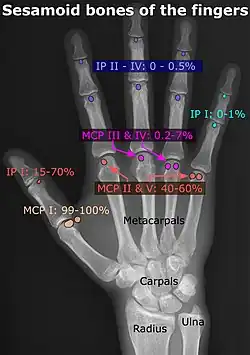

- In the hand—two sesamoid bones are commonly found in the distal portions of the first metacarpal bone (within the tendons of adductor pollicis and flexor pollicis brevis). There is also commonly a sesamoid bone in distal portions of the second metacarpal bone and fifth metacarpal bone.[7]

- ^ Chen W, Cheng J, Sun R, Zhang Z, Zhu Y, Ipaktchi K, et al. (2015). "Prevalence and variation of sesamoid bones in the hand: a multi-center radiographic study". Int J Clin Exp Med. 8 (7): 11721–11726. PMC 4565393. PMID 26380010.